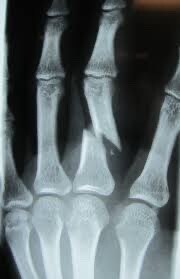

3. I don’t have footage of my very few attempts but I do have an illustration of how my hand feels when I try to execute one!

Post Image